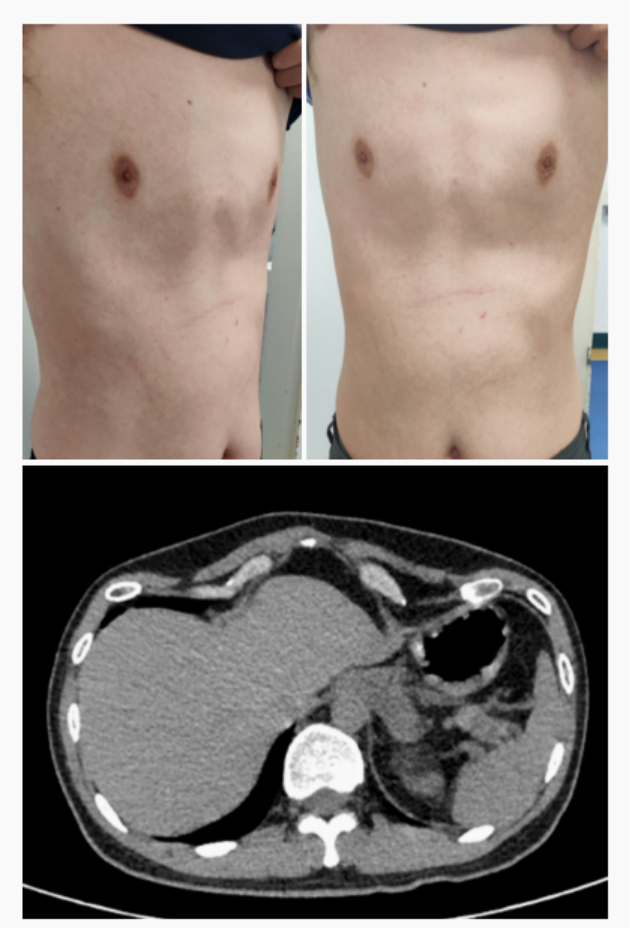

Saddle chest is a unique chest wall deformity characterized by symmetrical indentations on each side of the lower chest. These indentations are not connected and are separated by the normal height of the chest wall in the center, creating the appearance of a “saddle”. This condition, first named by Dr Wenlin Wang, is distinct from other chest deformities, requiring a thorough understanding for proper diagnosis and treatment.

Secondary saddle chest can develop after the Nuss procedure, a surgery typically used to treat pectus excavatum (a condition of an indented chest wall). While the Nuss procedure is highly effective for pectus excavatum, one potential complication is the formation of a saddle chest. The fundamental reason Nuss procedure leads to secondary saddle chest lies in its surgical principle. The Nuss procedure requires using steel bars to elevate the central depression, and the bars need appropriate support points. When the depression is excessively severe—meaning the bar bears excessive force—this force concentrates on the local ribs. If the ribs are sufficiently rigid, it typically won’t cause localized abnormalities. However, if the ribs lack sufficient stiffness, it can lead to localized depressions, resulting in the characteristic saddle chest deformity with bilateral depressions and a normally contoured central region.